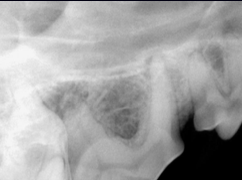

Quelles sont les lx?

Perte osseuse sur 404 et poche infra-osseuse sur 304